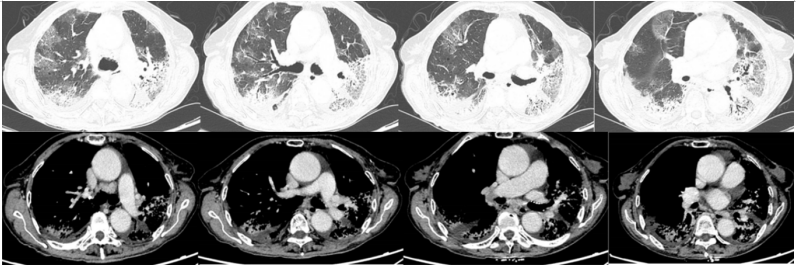

经过上述治疗,患者WBC、CRP、LDH、PCT均逐渐下降,肌酐正常。8月10日检查:WBC 9.1×109/L,CRP 6.8 mg/L,PCT 0.04 ng/ml,LDH 406 U/L。8月3-10日期间,患者心率持续变快,需要两种血管活性药物控制血压,无法进行俯卧位通气。ECMO上机前,患者右肺渗出性病变明显加重(图3)。

图3 患者床旁胸片变化情况